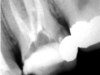

Conservativa: rilevamento della carie, anche con radiografia digitale o con strumento laser, ripristino della morfologia dentale in materiale estetico.

Endodonzia: rimozione della polpa dentale (nervo) dalla camera pulpare e dalla radice dentale e sigillatura con materiale inerte.

Implantologia: inserimento di impianti al posto delle radici del dente.